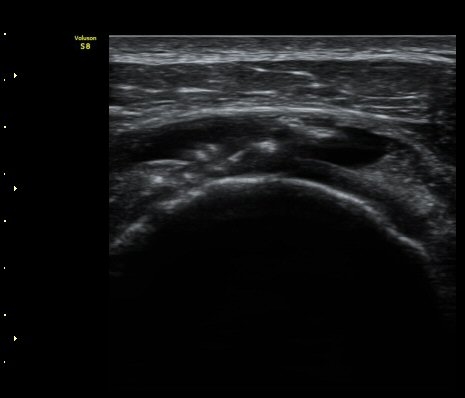

À̵ιڱ٠Ⱦ´Ü¸é°Ë»ç¿¡¼­ °üÀý³» ¼ö¾×Àú·ù´Â °üÂûµÇÁö ¾Ê´Â´Ù(»çÁø 1)